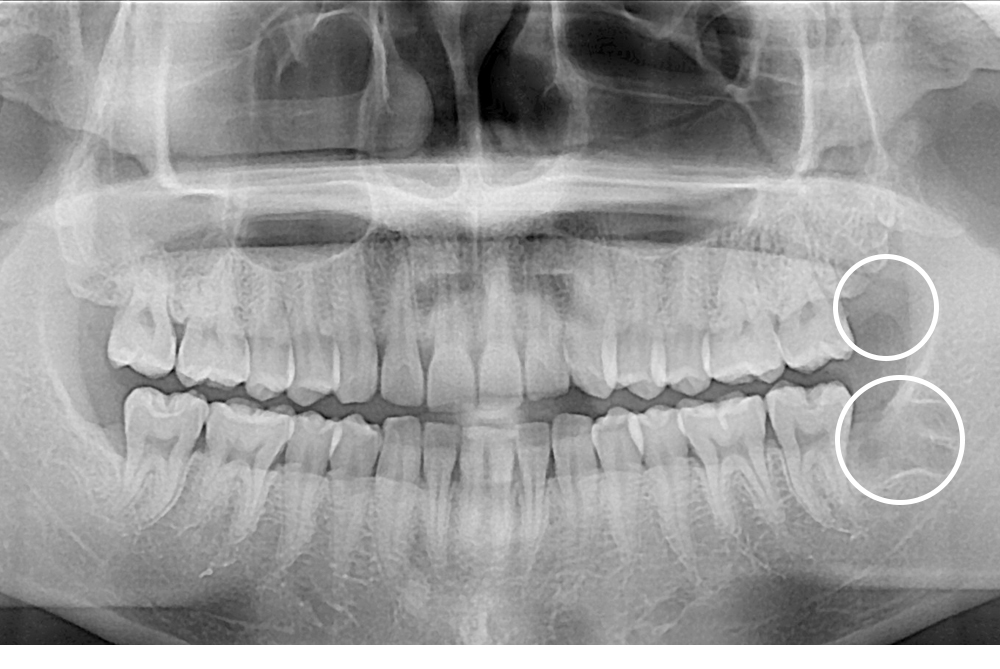

[사랑니] 매복 사랑니 발치

치료후 : 2017-12-08

세종치과는 구강악안면외과학 박사이신 원장님이 발치하는 치과입니다.